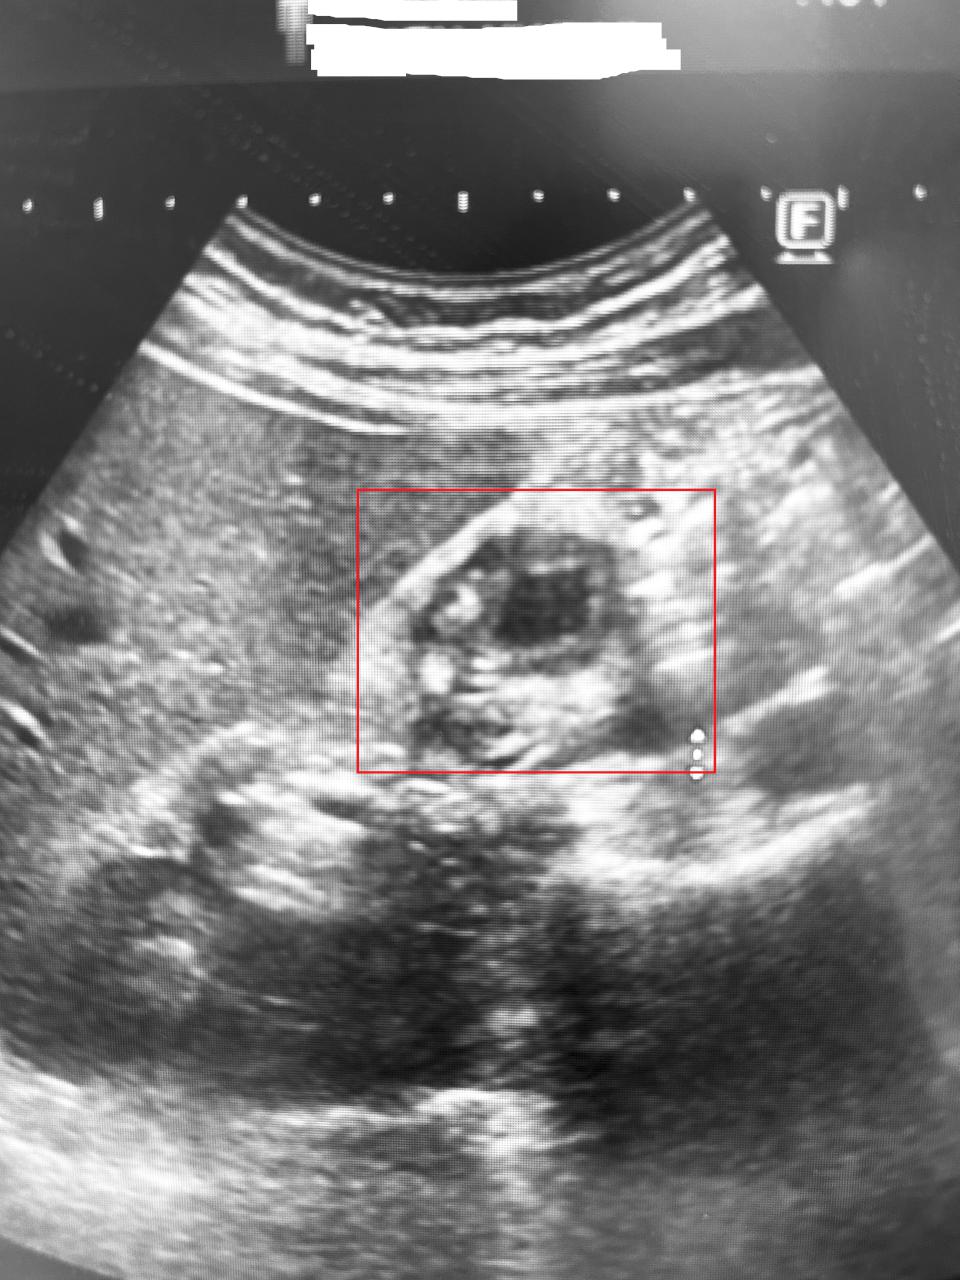

高市49歲林姓男子5年來飽受心窩悶痛與右上腹脹痛困擾,就醫檢查輕微胃炎且未發現結石,經博田國際醫院肝膽胰外科主治醫師李金德電腦斷層掃描發現膽囊壁異常增厚達正常6倍,進一步確診膽囊腺肌症,建議施作單孔腹腔鏡切除膽囊,術後復原情況良好,李金德說,50至60歲是膽囊腺肌症好發族群,女性略多男性,如長期飯後疼痛、噁心、腹脹、背痛等症狀,速就醫診療,重拾正常生活。圖/博田國際醫院提供、文/高培德